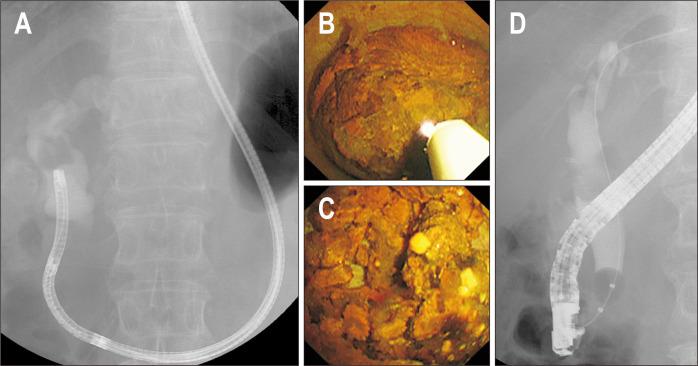

BACKGROUND/AIMS: Treatment options for difficult bile duct stones are limited. Direct peroral cholangioscopy (POC)-guided lithotripsy may be an option. A newly developed multibending (MB) ultraslim endoscope has several structural features optimized for direct POC. We evaluated the utility of direct POC using an MB ultraslim endoscope for lithotripsy in patients with difficult bile duct stones.

Twenty patients with difficult bile duct stones, in whom stone removal using conventional endoscopic methods, including mechanical lithotripsy, had failed were enrolled from March 2018 to August 2019. Direct POC-guided lithotripsy was performed by electrohydraulic lithotripsy or laser lithotripsy. The primary outcome was complete ductal clearance, defined as the retrieval of all bile duct stones after lithotripsy confirmed by balloon-occluded cholangiography and/or direct POC.

The technical success rate of direct POC was 100% (20/20), and the free-hand insertion rate was 95% (19/20). Direct POC-guided lithotripsy, attempted by electrohydraulic lithotripsy in nine patients (45%) and laser lithotripsy in 11 patients (55%), was successful in 95% (19/20) of the patients. Complete ductal clearance after direct POC-guided lithotripsy was achieved in 95% (19/20) of patients. Patients required a median of 2 (range, 1-3) endoscopic retrograde cholangiopancreatography sessions for complete stone removal. Adverse event was observed in one patient (5%) with hemobilia and was treated conservatively.